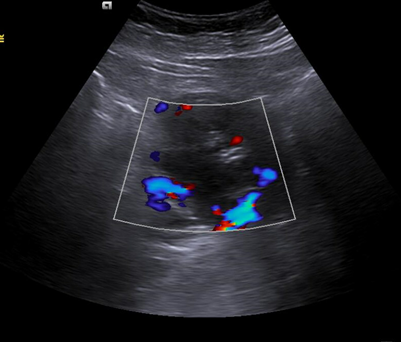

Hallazgos ecográficos

Riñón derecho 9,9 cm con morfología y ecogenicidad conservada. Presenta hidronefrosis grado III. No se identifica causa obstructiva.

Se remite a la paciente a Urgencias donde fue dada de alta con diagnóstico de CRU y tratamiento con Fosfomicina. Consultó al día siguiente, persistiendo el dolor y febrícula, remitiéndose de nuevo a Urgencias. Solicitan estudio de imagen con ecografía y ante los hallazgos se amplió el estudio a TC simple de abdomen: Hidronefrosis grado III con líquido perirrenal sugestivo de rotura de fórnix. Nefrolitiasis puntiformes en ambos cálices inferiores. Sin clara causa obstructiva objetivable. Se contactó con Urología de guardia quien propuso tratamiento ambulatorio con seguimiento posterior y colocación de nefrostomía programas y pielografía para estudio de probable estenosis de unión pieloureteral. Actualmente la paciente permanece en seguimiento por urología.